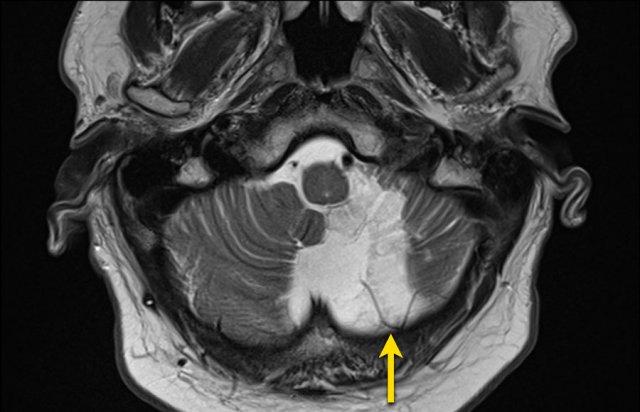

Bệnh nhân này nhập viện với xuất huyết tiểu não.

Các hình ảnh chuỗi xung gradient echo cho thấy nhiều vi xuất huyết.

Đây có thể là hậu quả của tăng huyết áp lâu năm do vị trí trung tâm của một số vi xuất huyết.